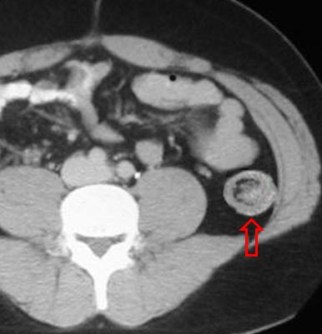

SIGNO DE LA ESCARAPELA

Signo de invaginación intestinal visible tanto en ecografía como en la TC abdominal, consistente en la imagen de bandas concéntricas de diferente ecogenicidad o densidad, correspondiente al asa invaginada en el interior de la invaginante, vista en un corte axial al asa. En ecografía, las bandas hiperecogénicas están formadas por la mucosa y la muscularis de la mucosa, y las hipoecogénicas corresponden a la submucosa.

En la literatura anglosajona, este signo es más frecuentemente descrito como Signo de la diana o Signo del donut.